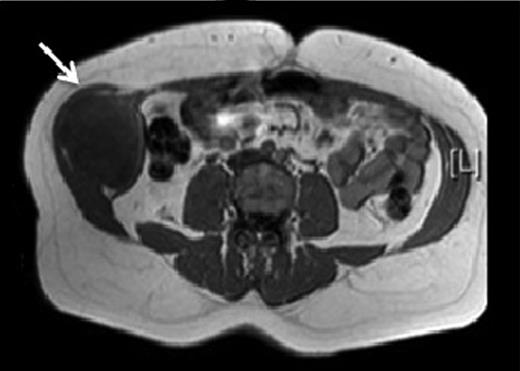

A 31-year-old man presented to his General Practitioner in May 2012 with a 6-week history of a painful mass in the right iliac fossa. There was no regional lymphadenopathy and hip examination was unremarkable. He was a smoker with a BMI of 33 and had undergone a right-sided inguinal hernia synthetic mesh repair in 2010. MRI with contrast confirmed a 6.9 × 6.7 × 4.6 cm mass invading the abdominal wall musculature (Fig. 4). Radiological features were suggestive of sarcoma or aggressive fibromatosis. Histology from an ultrasound-guided biopsy revealed aggressive fibromatosis. The patient opted for a surgical excision of the mass with abdominal wall reconstruction. The tumour was excised with the internal oblique, leaving the peritoneum and external ring cord structures intact. A 13 × 15 cm sheet of porcine intestinal biological mesh was used to repair the abdominal wall defect (Fig. 5). Inferiorly, the mesh was doubled over in the pre-peritoneal space to reconstruct the inguinal ligament, and sutured to the external oblique. The histology confirmed a final diagnosis of aggressive fibromatosis excised with 1 mm margins. At 24 months, there was good wound healing and no hernia, seroma or evidence of recurrence on follow-up MRI.

T1 MRI showing a soft tissue tumour of the anterior abdominal wall involving external oblique and internal oblique and not involving the peritoneum.